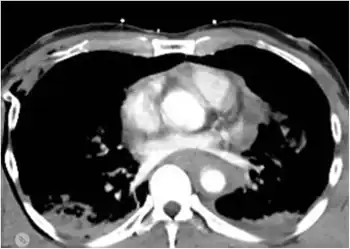

Though not completely reliable, chest X-rays are the first-line investigation,[4] initially used to diagnose this condition when the patient is unstable and cannot be sent to the CT bay. The preferred method of diagnosis used to be CT angiogram until it was found to cause complications in some people; now it is reserved for when CT scans are inconclusive.[4]

The classical findings on a chest X-ray will be widened mediastinum,[4] apical cap, and displacement of the trachea, left main bronchus, or nasogastric tube. A normal chest x-ray does not exclude transection, but will diagnose conditions such as pneumothorax or hydrothorax. The aorta may also be torn at the point where it is connected to the heart. The aorta may be completely torn away from the heart, but patients with such injuries rarely survive very long after the injury; thus it is much more common for hospital staff to treat patients with partially torn aortas.[1] When the aorta is partially torn, it may form a "pseudoaneurysm". In patients who do live long enough to be seen in a hospital, a majority have only a partially torn blood vessel, with the outermost adventitial layer still intact.[2] In some of these patients, the adventitia and nearby structures within the chest may serve to prevent severe bleeding.[2] After trauma, the aorta can be assessed by a CT angiogram or a direct angiogram, in which contrast is introduced into the aorta via a catheter.